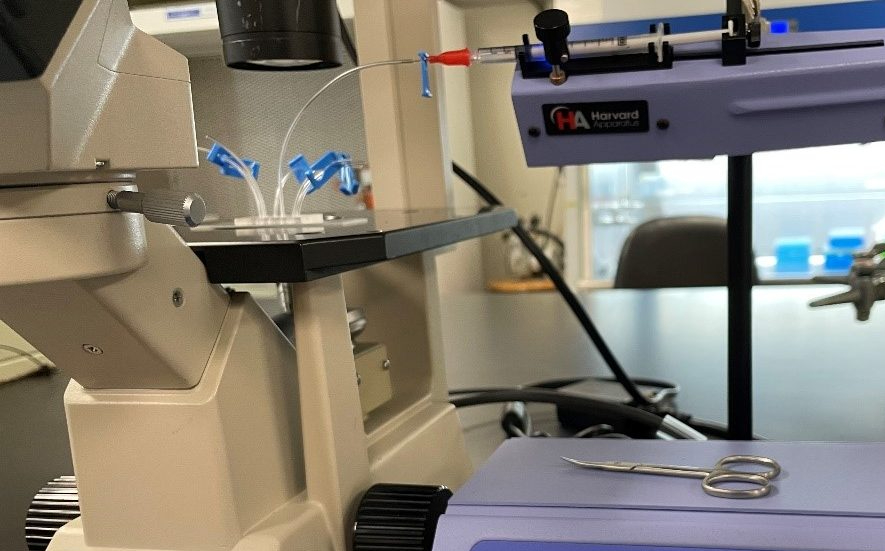

Project 1: Biomimetic Platform for Therapeutic Screening

Drug development and testing are expensive and laborious processes. Use of microfluidic devices can help alleviate those shortcomings. By using tumor-on-a-chip setups we are able to effectively measure drug characteristics such as diffusivity and efficacy in a replicated in vivo environment. This allows for detailed views into behaviors of drugs that might not be observed in traditional testing environments. By partnering with pharmaceutical professionals, we are able to expedite the traditional testing process and display the robustness of microfluidics testing.